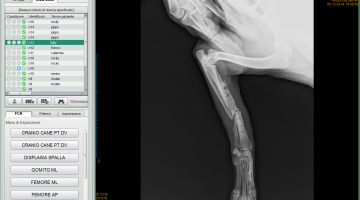

Attualmente la nostra struttura è munita di un apparecchio radiologico digitale indiretto Fuji. (Nella photogallery in basso). I vantaggi di questa tecnologia rispetto alla radiologia “analogica “ tradizionale sono molteplici. Primo fra tutti la qualità dell’immagine e la possibilità di ingrandire i particolari, correggere i contrasti, visualizzarla in negativo, ma anche misurare con precisione i dettagli. Poi la notevole riduzione dei tempi dello studio radiografico che in campo veterinario significa anche la riduzione dei tempi di anestesia del paziente con beneficio per la sua salute. Le lastre digitali non inquinano l’ambiente. Sono dei files che possono essere trasmessi per posta elettronica, masterizzati su cd o pennette di memoria da mettere nella cartella clinica da consegnare al proprietario del paziente e, nel caso della nostra struttura allegati in rete e nella scheda clinica dell’animale.